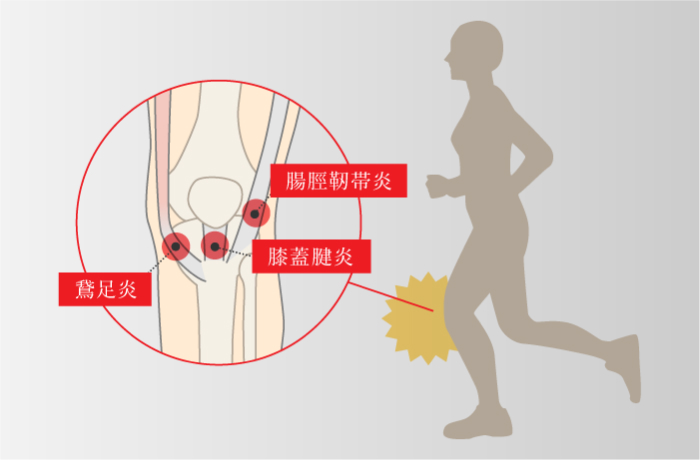

ジャンバーズニー(膝蓋腱炎)

ランナーズニー(腸脛靭帯炎)

靭帯がジャンプ動作や膝の曲げ伸ばし動作で繰り返しストレスが加わることで骨とこすれて損傷し、炎症を起こして痛みなどが生じる。

鵞足炎

-

膝の関節のすぐ下にある脛骨につながっている3つの腱(筋肉と骨をつなぐ組織)。この形状がガチョウの足のようにみえることから「鵞足」と呼ばれる。 繰り返しの曲げ伸ばしで靭帯や腱が骨との摩擦によって傷つき、炎症を起こすことがある。

※主な関連する筋肉は縫工筋・薄筋・半腱様筋